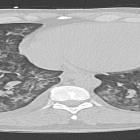

Dilated

cardiomyopathy secondary to chronic cocaine abuse: a case report. Computed tomography of the chest without contrast - bilateral peribronchovascular airspace consolidation, ground-glass opacity with interlobular septal thickening.